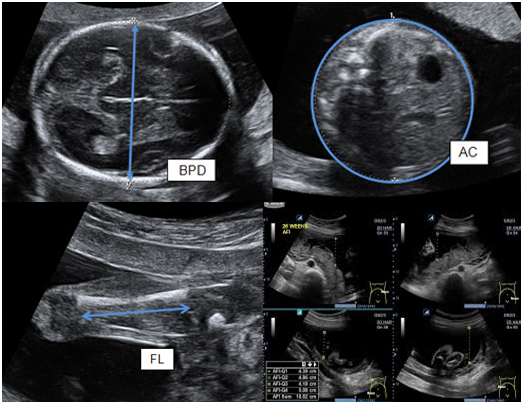

கருவின்வளர்ச்சியை ஸ்கேன்செய்யும்போது, கருவின்பல்வேறு அளவீடுகள்எடுக்கப்படுகின்றன. கர்ப்பிணிகள்ஸ்கேன் செய்யும்போது (கர்ப்பகாலவயது) கர்ப்பமாக இருக்கும்வாரங்களின் எண்ணிக்கைக்குஏற்ப அளவீடுகள்வளர்ச்சி அட்டவணையில் திட்டமிடப்பட்டுள்ளன. வளர்ச்சிஸ்கேனுக்காக எடுக்கப்பட்ட முக்கியகருவின் அளவீடுகள் பின்வருமாறு:

- இருமுனைவிட்டம் (BPD) தலைமுழுவதும் அளவிடப்படுகிறது

- தலைசுற்றளவு (HC) – தலையைச்சுற்றி அளவிடும்

- அடிவயிற்றுசுற்றளவு (AC) – அடிவயிற்றைச்சுற்றியுள்ள அளவீடுகள்

- தொடைஎலும்புநீளம் (FL) – தொடைஎலும்பின் நீளத்தை அளவிடுகிறது

கருவின்எடையின் (EFW) மதிப்பீட்டைமேற்கூறிய அளவீடுகளைஇணைத்து கணக்கிடலாம்.EFW ஆனது, கருசராசரியாக உள்ளதா, பெரியதா அல்லது அதன்கர்ப்பகாலவயதிற்கு சிறியதாஎன்பதை தீர்மானிக்கஉதவும் வரைபடத்தில் திட்டமிடப்பட்டுள்ளது. கருவின் எடைமதிப்பீடுவரை படத்தில் கீழே உள்ள 10% வரிக்குக்கீழே இருந்தால், அதுகர்ப்பகால வயதுக்கு (SGA) சிறியதாகக்கருதப்படுகிறது.கருவின் எடை வரைபடத்தில்முதல் 10 சதவீத வரிக்குமேல் இருந்தால், அதுகர்ப்பகாலவயதுக்கு (LGA) குறிப்பிடத்தக்கதாகக்கருதப்படுகிறது.